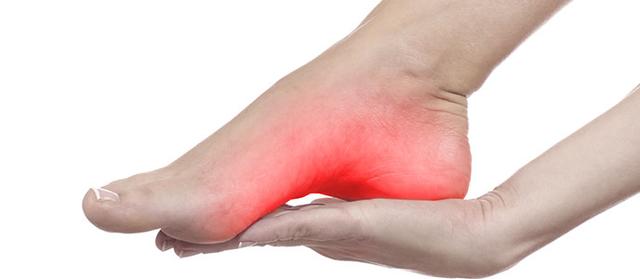

利尿劑能夠致使痛風發作其實很好理解,利尿後外周循環血容量降低,腎小球濾過率降低,代償性的近曲小管重吸收作用增加,可能使得尿酸排泄減少,在臨床上能遇到很多痛風患者,長時間沒有發病,因為服用了利尿劑後致使痛風再犯。